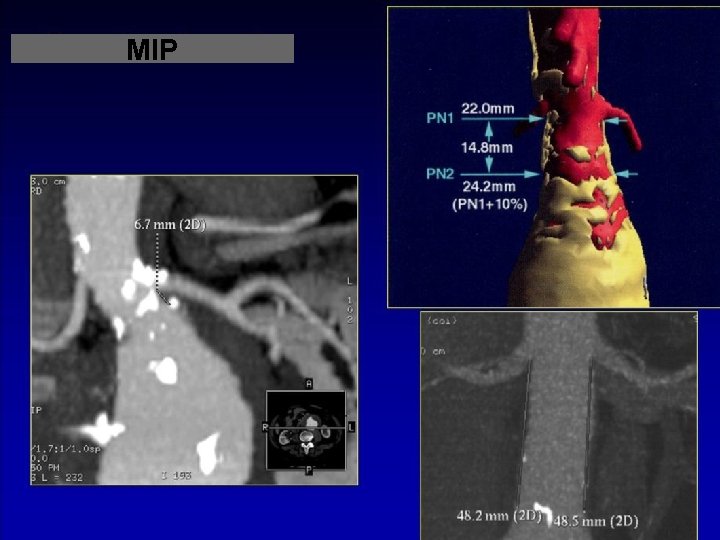

MIP